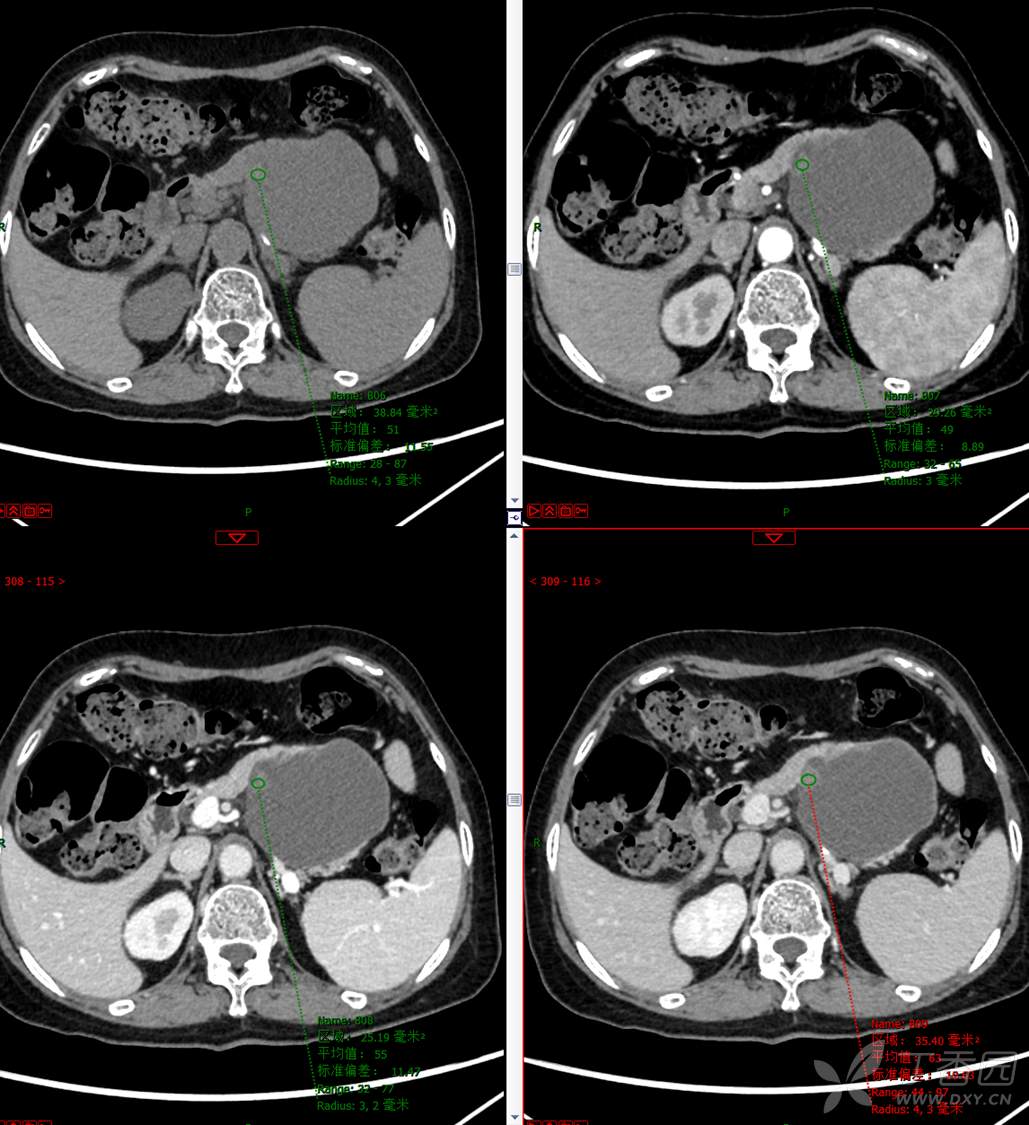

主 诉:发现胰腺占位性病变3月

现病史:患者3月前就诊于**市人民医院行腹部增强CT发现胰尾占位性病变,无腹痛、腹胀,无恶心呕吐,无黄疸,无呕血黑便,无胸闷憋气,无寒战高热,未行特殊治疗